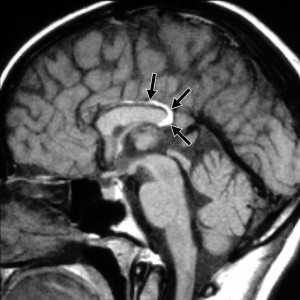

МРТ головного мозга. Т1-взвешенные корональная и сагиттальная МРТ. Эпидермоидная киста левой височной доли.

При МРТ головного мозга картина неспецифическая и зависит от содержимого кисты. Если она не содержит жира, то имеет ликворную интенсивность сигнала . В таком случае эпидермоидная киста трудно отличима от арахноидальной, хотя, как правило, не столь однородная. На МРТ типа FLAIR и диффузионно-взвешенных МРТ изображениях содержимое эпидермоидов светлее ликворного. Жировое содержимое, такие эпидермоиды еще называют холестеатомой, приводит к высокому сигналу на Т1-взвешенных МРТ головного мозга. Видимо, он обусловлен липидами, но не холестеролом. На Т2-взвешенных МРТ головного мозга он менее интенсивен чем ликвор. Контуры эпидермоидов всегда четкие. Холестеатомы составляют всего 3-5% от эпидермоидов. В 15-20% случаев встречается кальцификация по переферии кисты. Редко наблюдается контрастирование стенок.

При МРТ головного мозга картина неспецифическая и зависит от содержимого кисты. Если она не содержит жира, топри МРТ головного мозга эпидермоидная киста имеет ликворную интенсивность сигнала. В таком случае эпидермоидная киста трудно отличима от арахноидальной, хотя, как правило, не столь однородная. На FLAIR томограммах и диффузионно-взвешенных МРТ головного мозга содержимое эпидермоидов светлее ликворного. Жировое содержимое, такие эпидермоиды еще называют холестеатомой, приводит к высокому сигналу на Т1-зависимых МРТ головного мозга. Видимо, он обусловлен липидами, но не холестеролом. На Т2-взвешенных МРТ головного мозга он менее интенсивен чем ликвор. Контуры эпидермоидов на МРТ всегда четкие. Холестеатомы составляют всего 3-5% от эпидермоидов. В 15-20% случаев встречается кальцификация по переферии кисты. Редко наблюдается усиление стенок кисты при МРТ головного мозга с контрастированием.